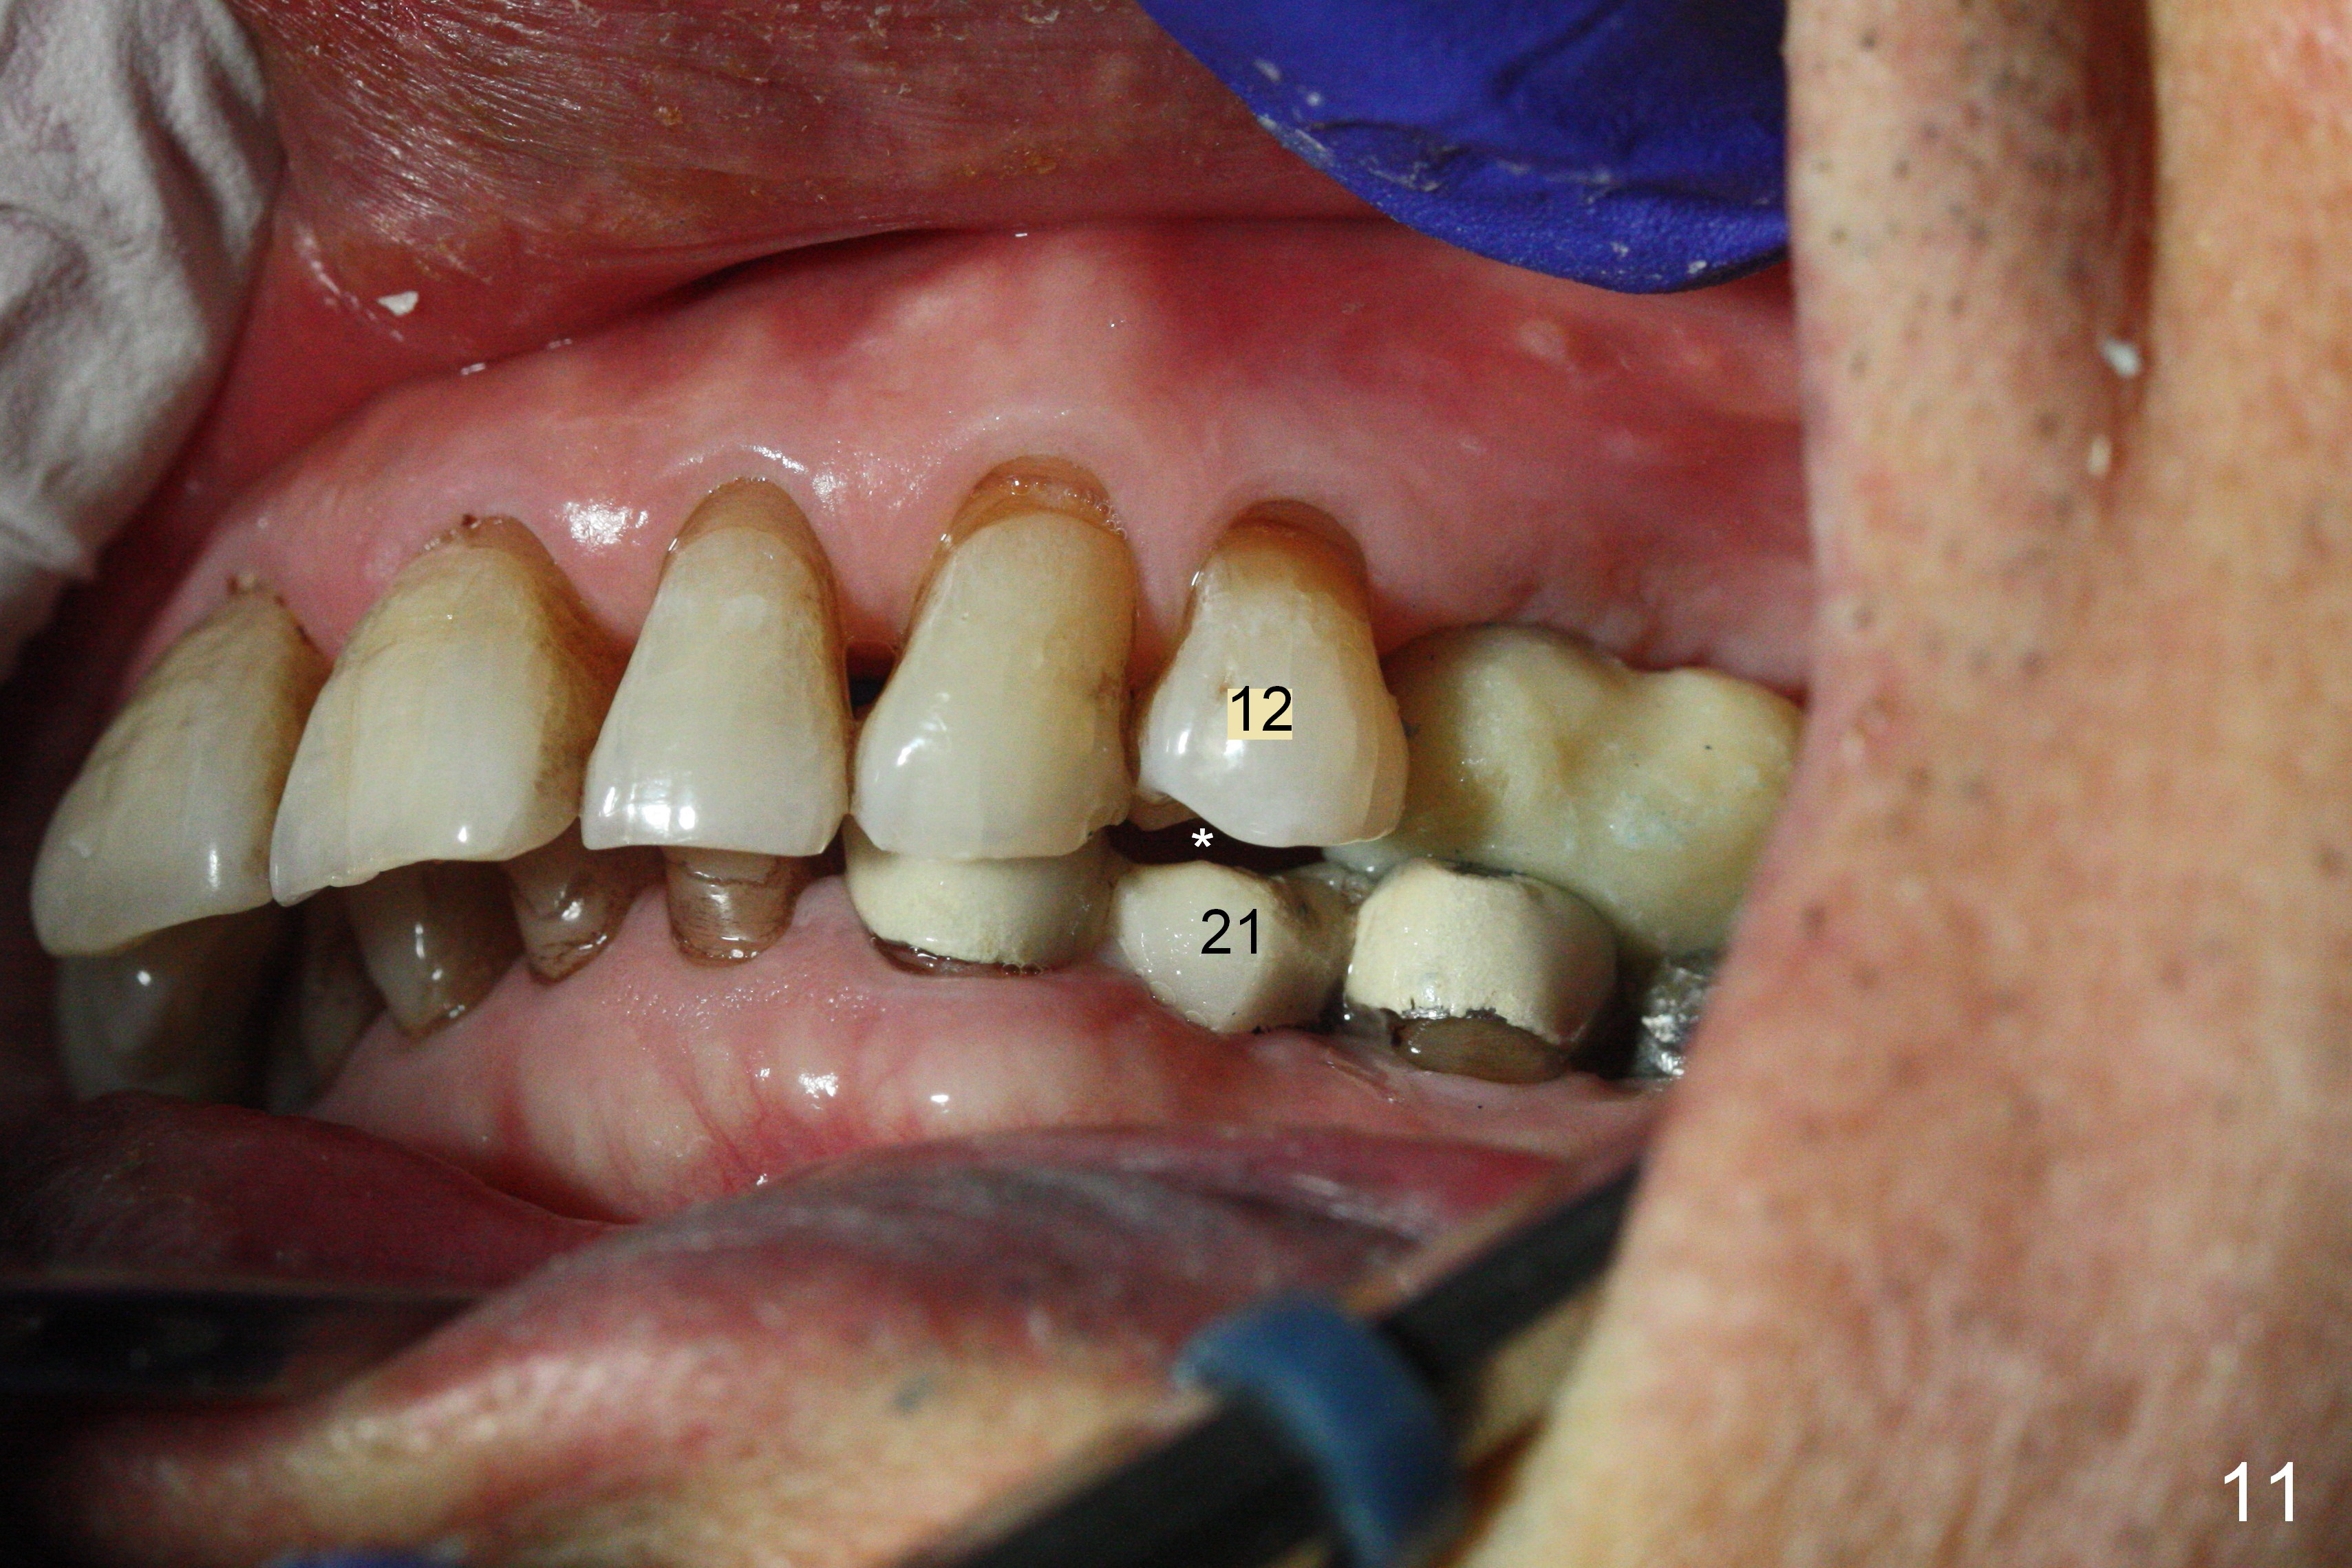

The fistula buccal to #14 remains 1 week postop (Fig.7) and disappears 1 months postop. The fistula does not re-appears 3 months postop with the implants at #13,15 apparently osteointegrated (Fig.8). With relining #13-15 provisional with increased vertical height (Fig.11), the patient has bilateral posterior contact (Fig.9), while the lower incisors do not contact the cinguli of the upper incisors (Fig.10 *). The space between the tooth #12 and the pontic #21 is unfavorable for posterior occlusal stability (Fig.11 *). Porcelain is chipped off the buccal surface of the pontic (Fig.12 *). If the patient does not afford an implant at #21 with redo crowns at #20 and 22 (Fig.13), what else could be done? He will return for #15 implant placement 4 months post socket preservation.